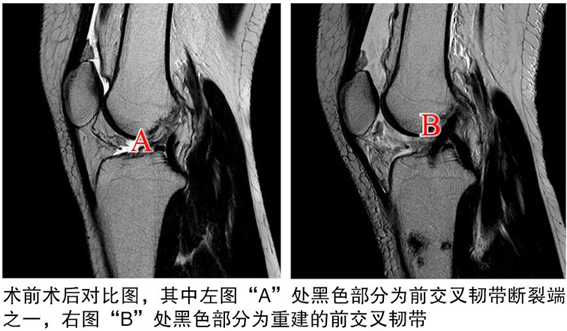

術(shù)后

關(guān)節(jié)鏡下見重建的前交叉韌帶